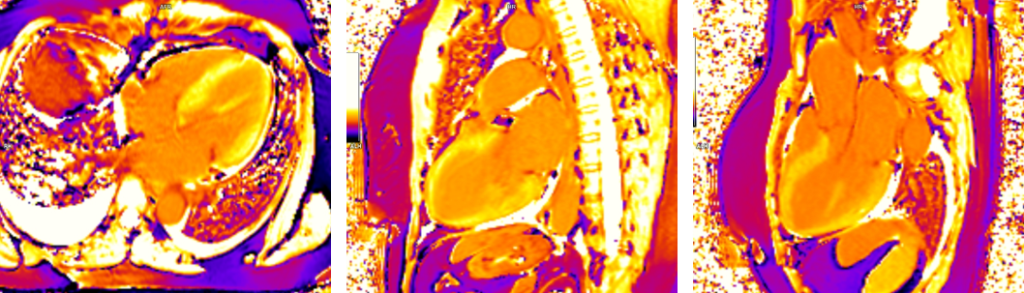

Figura 4: Secventa de edem (achizitie T2 cu saturatia grasimii)

Figura 5: Postcontrast achizitie tripla inversie-recuperare in ax scurt